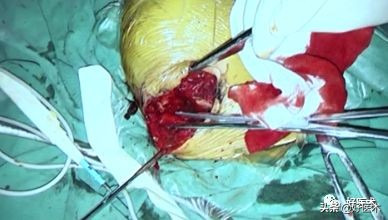

- 首先探查肩锁关节,显露脱位的肩锁关节,脱位程度三星以上,试行复位

- 牵引线依次从胸小肌、联合腱、喙肩韧带后方绕过喙突

- 喙锁韧带两侧边缘锁骨钻孔,牵引线穿过骨孔

- 肌腱依次绕过喙突及锁骨骨孔,打结固定并缝合

- 肌腱进一步加强肩锁关节